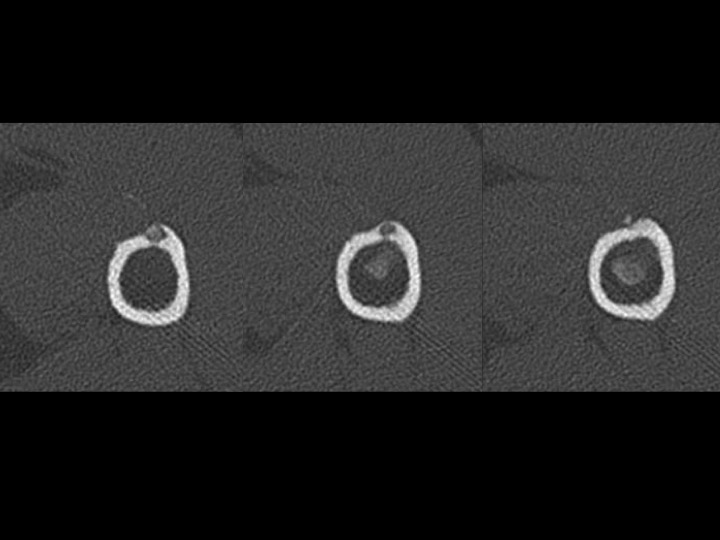

Fell 2 months earlier with minor persistent symptoms, acutely worse x 3 days opening a door. He reported night pain and pain with reaching. 80% improved after 2 days on Medrol dose pak. MRI shows subcortical humeral shaft marrow and parosteal edema with dark signal foci in the region of the pectoralis major insertion. CT shows both peri-tendinous calcifications as well has HADD deposits eroding through the cortex and into bone. Axillary XR clearly shows the peri-tendinous deposit; the cortical erosion is faintly visible....and I expect you can all see the intra-osseous calcific deposit.

tendon of pectoralis major ( RID2007 )